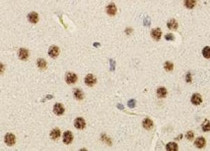

anti-Smad 5 antibody for IHC-Formalin-fixed paraffin-embedded sections,Western blot and Human,Mouse,Rat

| 应用 | IHC-P, WB |

检测图片 (1) Click the Picture to Zoom In